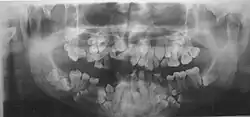

Panoramic view of the jaws showing multiple unerupted supernumerary teeth mimicking premolar, missing gonial angles and underdeveloped maxillary sinuses in cleidocranial dysplasia.

Panoramic view of the jaws showing multiple unerupted supernumerary teeth mimicking premolar, missing gonial angles and underdeveloped maxillary sinuses in cleidocranial dysplasia. -